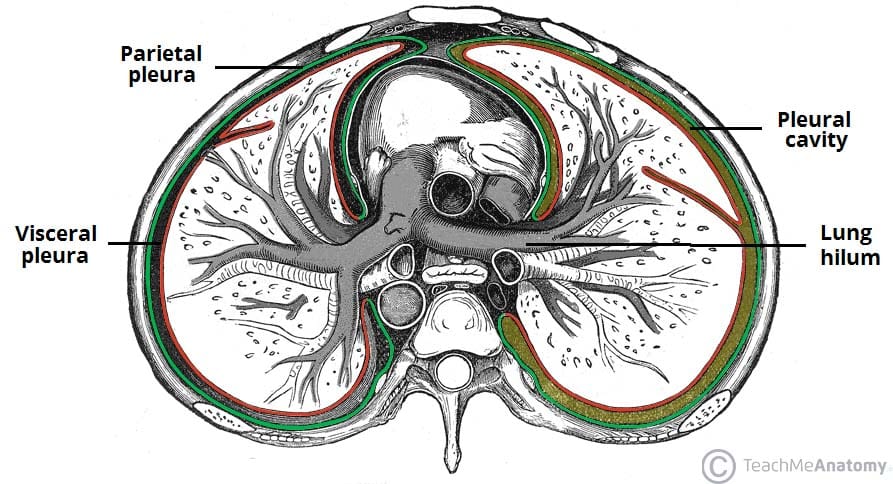

Each pleura can be divided into two parts:

• Visceral pleura – covers the lungs.

• Parietal pleura – covers the internal surface of the thoracic cavity.

These two parts are continuous with each other at the hilum of each lung. There is a potential space between the viscera and parietal pleura, known as the pleural cavity.

The visceral pleura covers the outer surface of the lungs, and extends into the interlobar fissures. It is continuous with the parietal pleura at the hilum of each lung (this is where structures enter and leave the lung).

Fig 1.1 - The parietal and viscera pleura, and the pleural cavity. Note how the two layers of pleura are continuous at the hilum of the lung.

The parietal and viscera pleura, and the pleural cavity. Note how the two layers of pleura are continuous at the hilum of the lung.